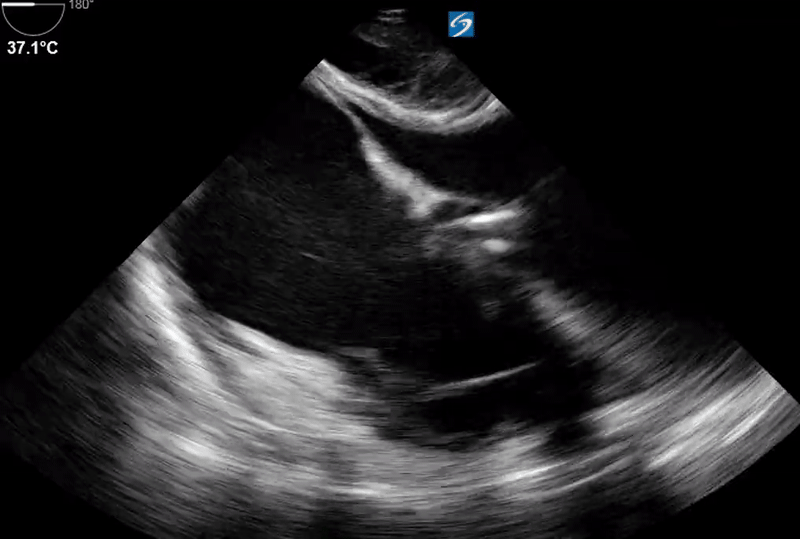

Transthoracic echocardiography (TTE) was difficult to perform due to the patient's post-operative condition but revealed that the Impella was abutting the septal wall. Despite repositioning, there was only a minimal improvement in flow. The patient's hemodynamic status continued to deteriorate. Given these findings, a transesophageal echocardiogram (TEE) was performed and showed:

The diagnosis in this case is localized pericardial tamponade, and the next best step in management is mediastinal re-exploration with evacuation of the hematoma. Post-operative complications in cardiac surgery are varied and can include graft failure, bleeding, unstable arrhythmias, sepsis, and pulmonary embolism. Patients receiving systemic anticoagulation are at higher risk for pericardial hematoma, a potentially life-threatening complication.

Classic signs of tamponade, such as Beck’s triad (muffled heart sounds, pulsus paradoxus, and jugular venous distention), may not always be clinically apparent. Additionally, tamponade can be difficult to diagnose, particularly when the effusion is localized to the posterior or lateral aspects of the pericardium. This makes it poorly visualized on a TTE, especially in the post-operative period. Conventional tests, such as electrocardiogram and chest X-ray, may also be suboptimal in diagnosing this condition.

A large circumferential pericardial effusion or an acute smaller effusion may raise concerns for tamponade physiology, but it is important to remember that localized pericardial effusions can also lead to tamponade by causing regional chamber compression. This type of effusion, along with hematomas, thrombus, or masses, can result in cardiac tamponade.

TEE is a critical diagnostic tool in this setting, as it offers better image quality, especially in post-operative patients. It also facilitates improved visualization of the posterior heart, which is often challenging to assess with TTE. Given the patient's high risk of tamponade, early use of TEE can assist in rapid diagnosis, leading to timely interventions that can be lifesaving.